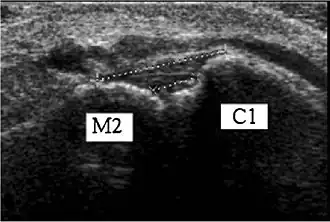

Ultrasonography of the dorsal Lisfranc ligament.[1]

C1 = Medial cuneiform

M2 = 2nd metatarsal base